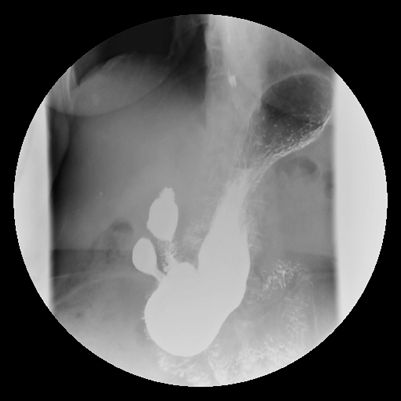

右前斜位(RAO)

躺臥位時,食道的鋇劑填充比較完全。

胃體部與幽門充滿鋇劑。

顯示出十二指腸球。

後前位(PA)

胃體部與幽門充滿鋇劑

幽門部會靠近影像中心n

右側位(right lateral)

體部與幽門充滿鋇劑。

可見幽門及十二指腸的C環。

可呈現胃後腔